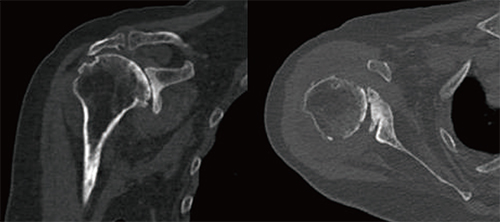

그림 4, Glenoid reaming 후 남은 bone이 거의 없어 glenoid baseplate를 삽입하기 어려워져서

humeral head cortical bone을 이용하여 augmentation 시행했다.

저자는 Glenoid의 glenoid vault가 14mm로 bone loss가 심한 Cuff tear arthropathy 환자에게 Navigation guided technique을 이용하여 Cortical bone augmentation을 시행하고 Glenoid baseplate를 성공적으로 고정하였고, 이 case를 공유하고자 한다. 81세 여환으로 Massive cuff teararthropathy(Hamada classification 5) 진단되었다. Glenoid의 bone loss가 심해서 인공관절의 glenoid baseplate를 삽입하기 힘든 구조였고(그림1) 이를 보완하기 위해 수술 시 Humeral head cutting시 생기는 cortical bone으로 glenoid에 augmentation을 시행하고 위에 baseplate를 대서 적절한 위치에 삽입하도록 계획을 세웠다. 예상대로 glenoid의 bone loss가 심하여 reaming이후에 baseplate를 삽입할 surface가 거의 남지 않았고 screw의 방향이 정확하게 가는 지 확인할 방법이 없었다. 하지만 Navigation(그림 2)의 guide에 따라 남아있는 glenoid의 bone stock에 최대한 긴 screw를 fixation 하였고 수술전에 planning 한대로(그림 3) humeral head의 cortical bone을 이용하여 augmentation을 시행한 뒤(그림 4)에 baseplate를 위치시켰고, 결과적으로 적절한 길이의 screw가 삽입될 수 있어 성공적으로 수술을 마쳤다. 수술 X-ray에서 인공관절이 수술 전 계획했던 대로 환자의 해부학적 위치에 맞게 제 위치에 적절히 삽입되었음을 확인할 수 있었다. 수술 후 cortical bone augmentation과 glenoid surface의 bone union이 촉진되도록 parathyroid hormone제제를 사용했다. 재활은 수술 후 환자는 bed side에서 pendulum 및 scapular stretching exercise를 자가 시행하였으며, 수술 1개월 후 보조 막대기를 이용하여 passive forward elevation 및 abduction을 했다. 수술 3개월 후 active shoulder ROM exercise를 시행했으며 수술 6개월 후 nearly full ROM을 회복하였다. 현재 환자는 수술 부위 통증도 거의 없으며 평소에 불편해하던 반대쪽 어깨도 수술 받고 싶어할 정도로 만족도가 높다.